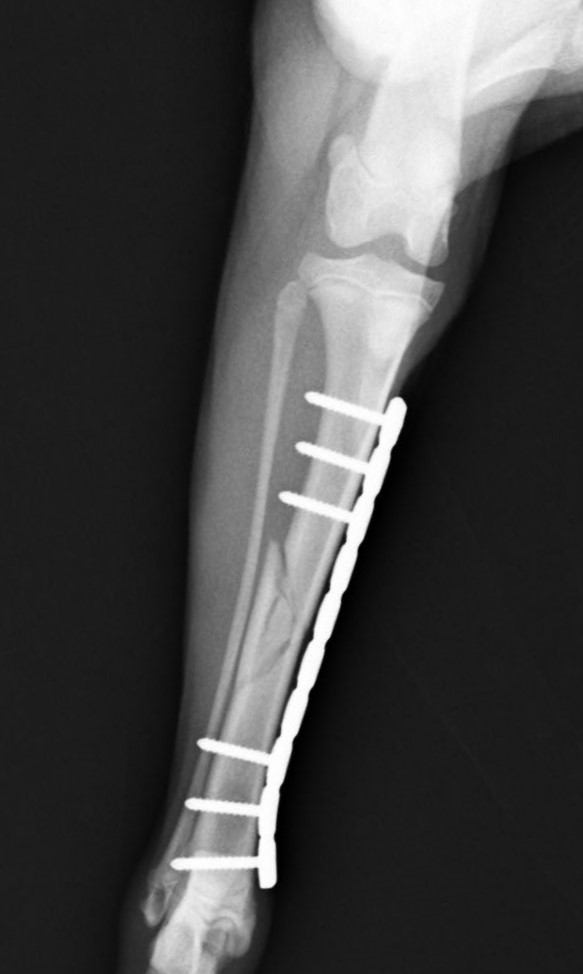

落下事故で右足の脛を骨折したワンちゃんが来院されました。ロッキングプレートであるMATRIX2.5と2.4スクリューで手術し、無事元気に歩いて退院していきました。よかったね。